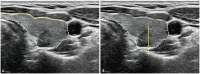

Active surveillance (AS) has been widely adopted as an alternative to immediate surgery owing to the indolent nature and favorable outcomes of papillary thyroid microcarcinoma (PTMC). AS is generally recommended for tumors measuring ≤1 cm without aggressive cytological subtypes, risk of gross extrathyroidal extension (ETE), lymph node metastasis (LNM), or distant metastasis. AS requires careful patient selection based on various patient and tumor characteristics, and ultrasound (US) findings. Moreover, during AS, regular US is performed to monitor any signs of tumor progression, including tumor growth, new US features of potential gross ETE, and LNM. Therefore, appropriate imaging-based assessment plays a crucial role in determining whether AS or surgery should be pursued. However, detailed recommendations concerning US evaluation are currently insufficient, necessitating the formulation of this guideline. The Korean Society of Thyroid Radiology has developed a consensus statement for low-risk PTMC, covering US assessment methods when considering AS as a management option and conducting follow-up imaging tests during AS. This guideline aims to provide optimal scientific evidence and expert opinion consensus regarding a standardized US-based assessment protocol for low-risk PTMC.